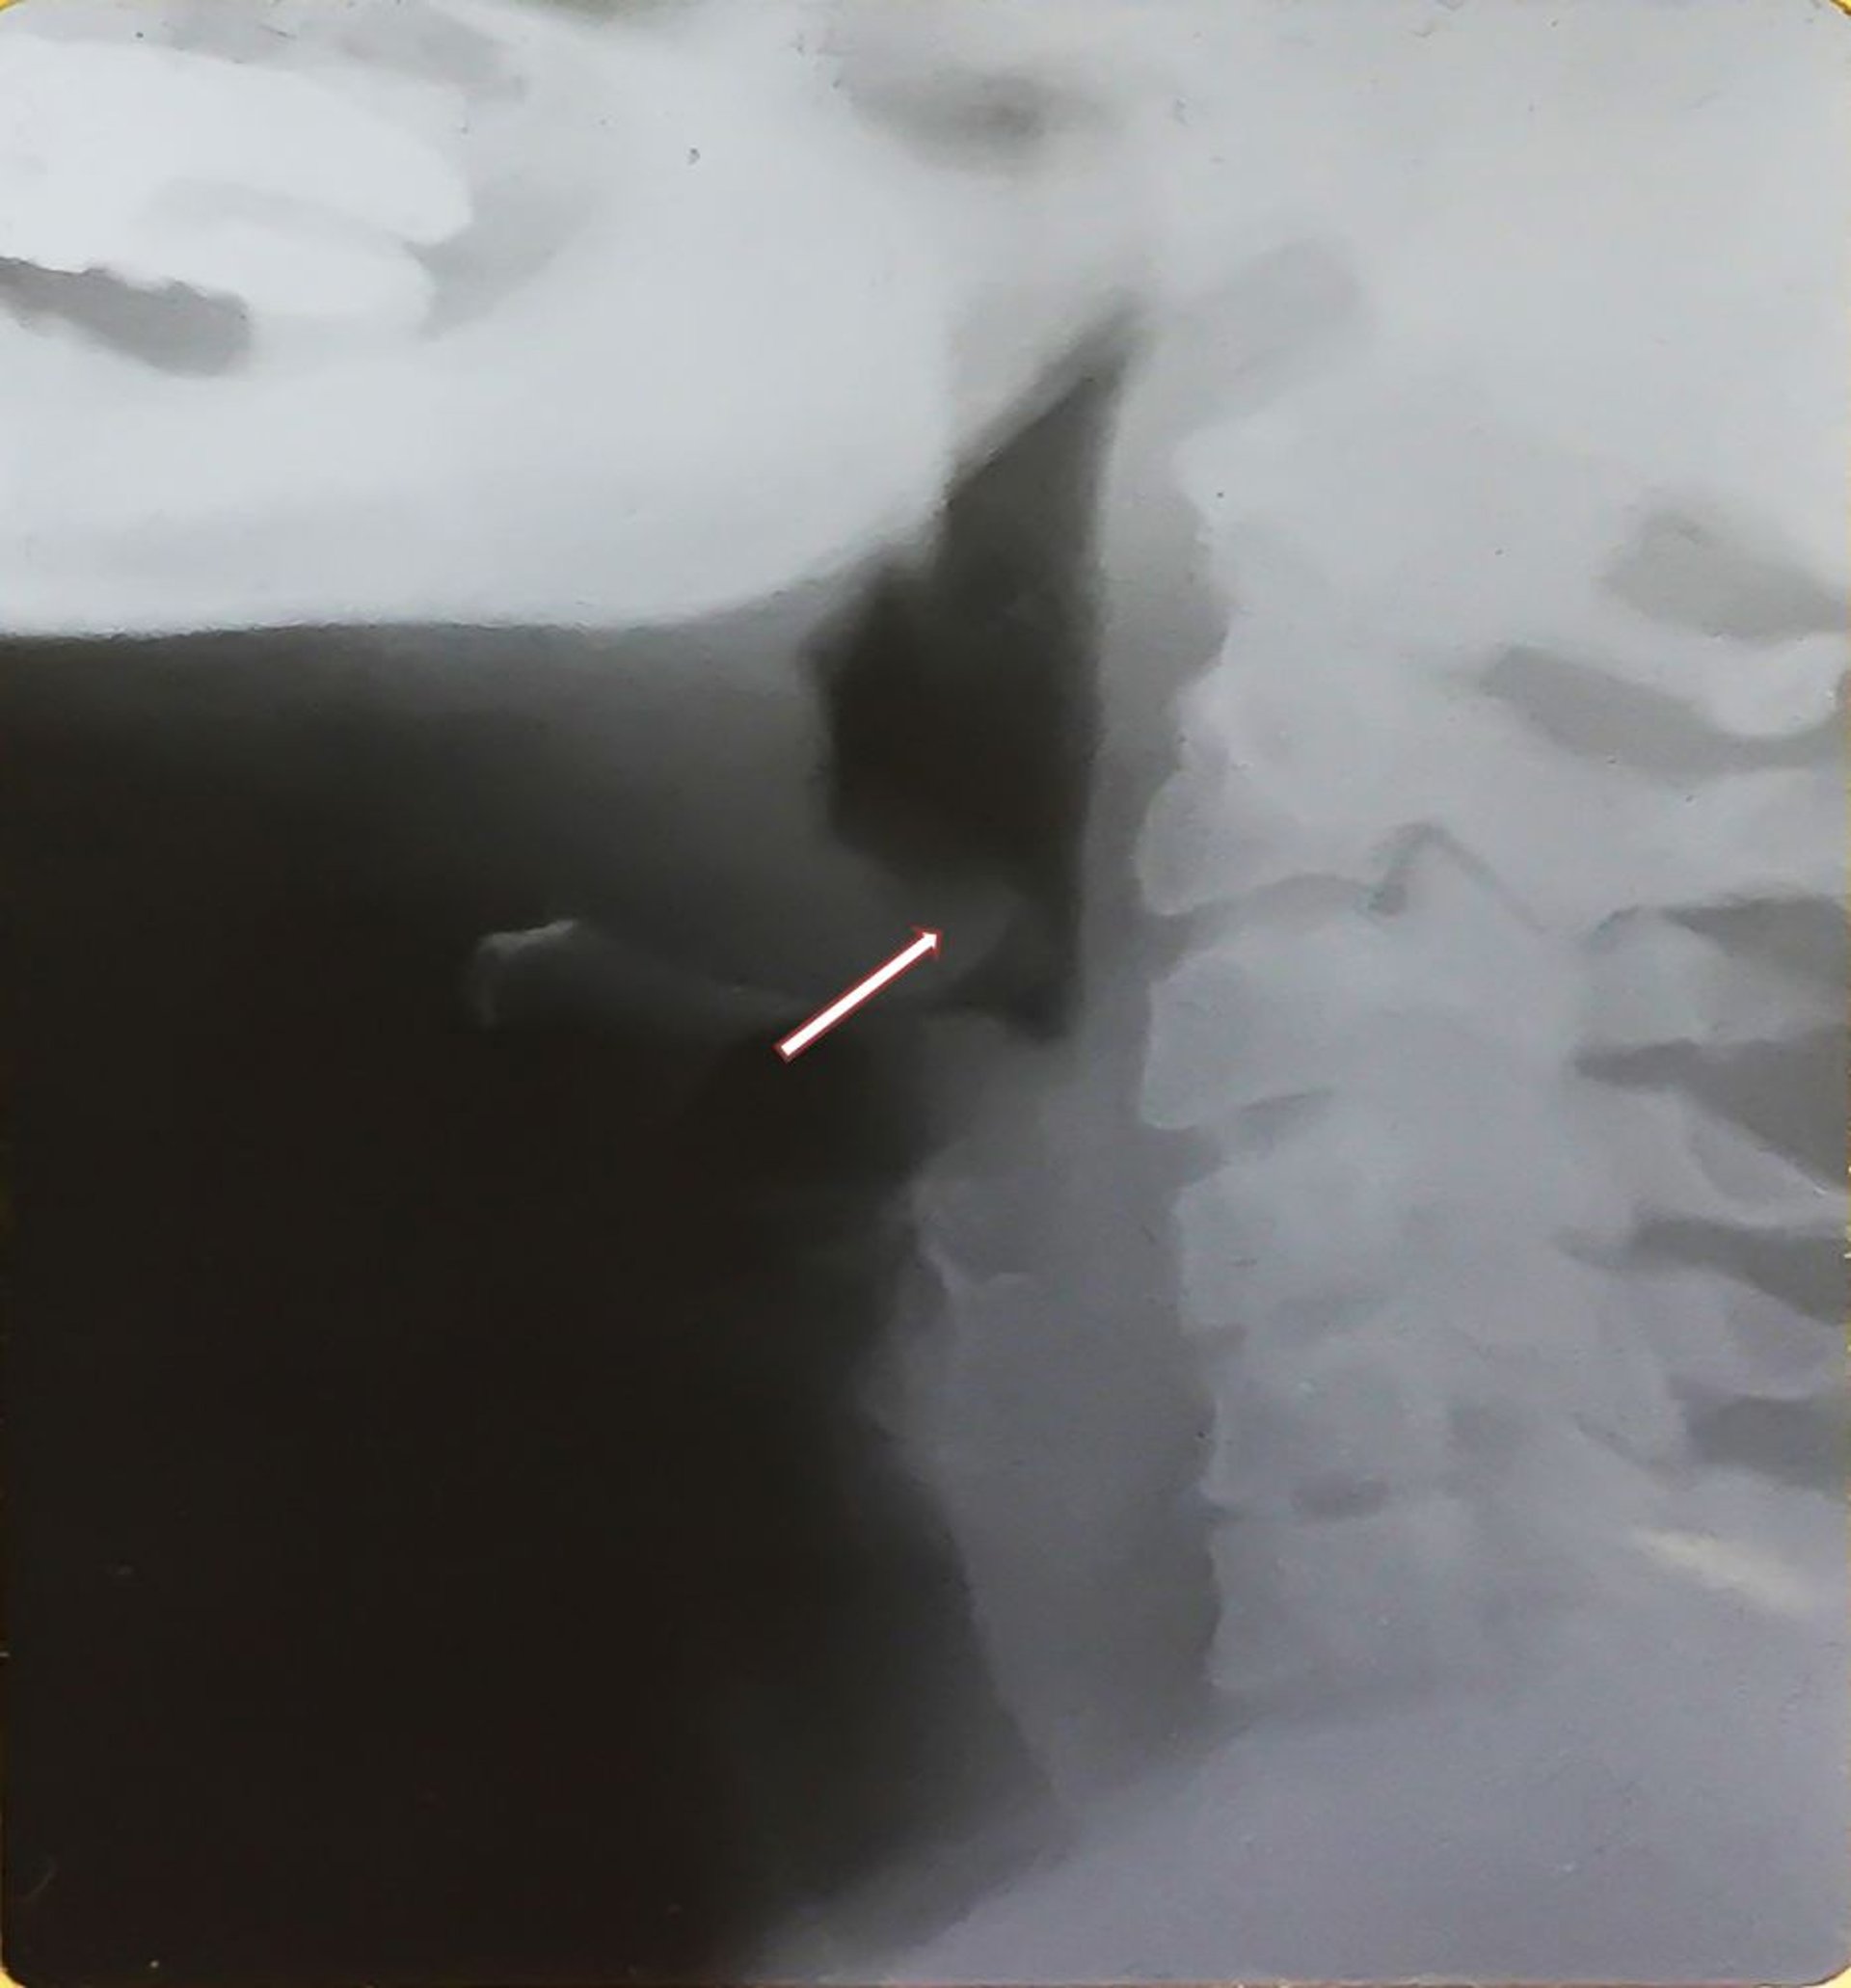

喉頭蓋炎(成人)

このX線写真には,喉頭蓋炎に特徴的な腫大した喉頭蓋(thumb sign―矢印)と下咽頭の腫脹が認められる。後方に偏位している肥厚した喉頭蓋に注意すること。

Image provided by Clarence T.Sasaki, MD.